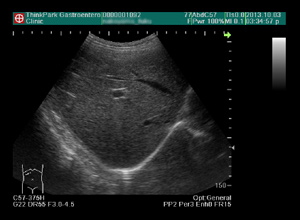

ThinkPark消化器クリニック| 腹部エコー、前立腺エコー

肝臓(脂肪肝、血管腫、肝炎、肝硬変、肝がんなど)、胆嚢(胆石、胆のうポリープなど)、腎臓、膵臓、膀胱、前立腺(前立腺肥大)、さらに子宮などを検査することができます。このような早期の病変をとらえるために、エコー検査をお勧めします。朝食を食べずに空腹であれば受診時にそのまま検査できます。

腹部エコー、前立腺エコー